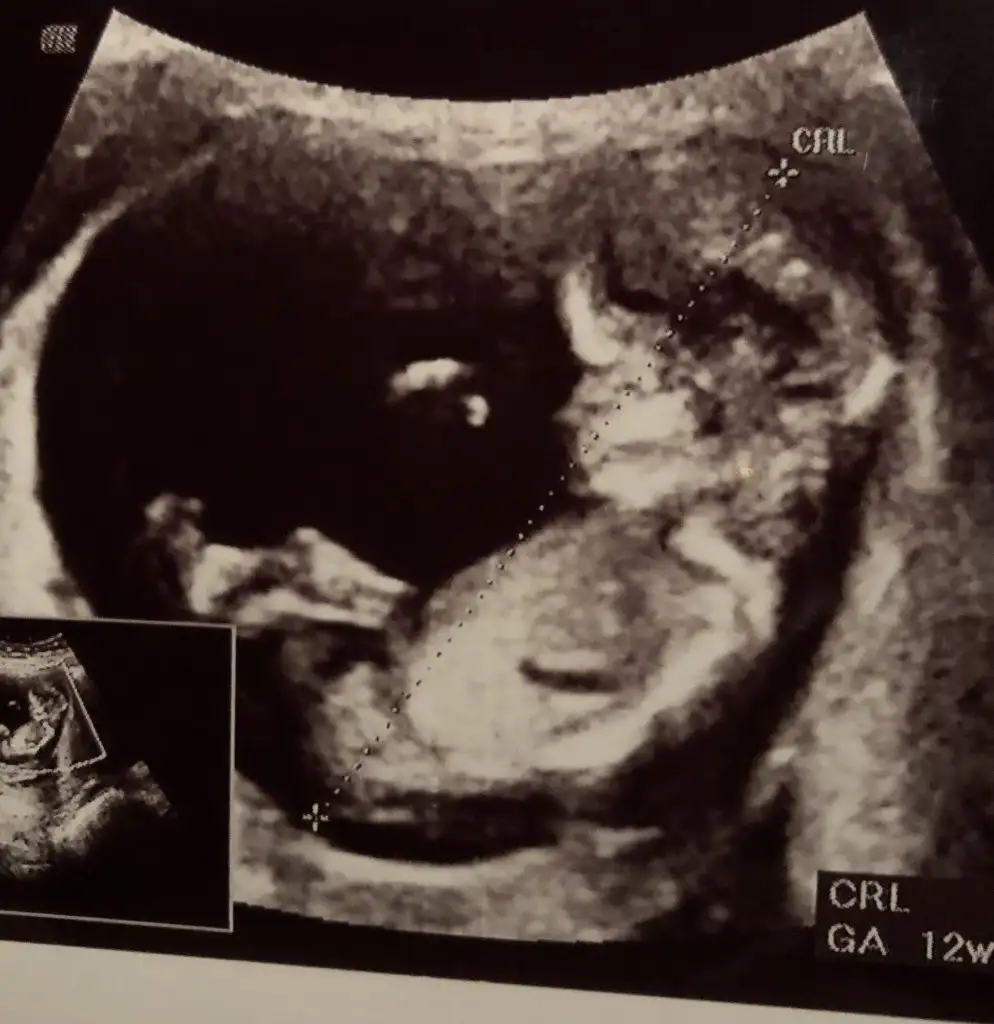

dr soylemeden siz gorun genital nub teorisi ( bebegin cinsiyeti)

Kaç haftada dedi cnm birde anketi kullanırsanız sevinirim 😊

14+3 de dedi erkek diye